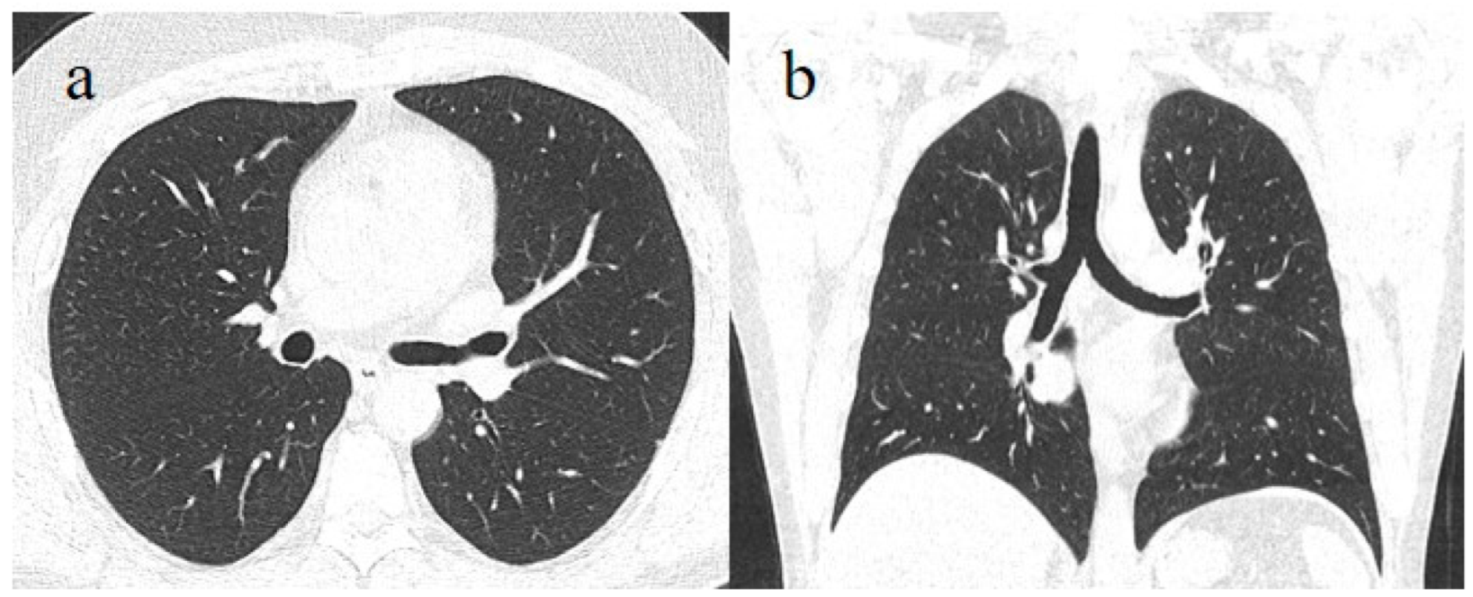

- Brogna, B.; Bignardi, E.; Brogna, C.; Capasso, C.; Gagliardi, G.; Martino, A.; Musto, L.A. COVID-19 Pneumonia in Vaccinated Population: A Six Clinical and Radiological Case Series. Medicina 2021, 57, 891. [Google Scholar] [CrossRef]

- Brogna, B.; Brogna, C.; Petrillo, M.; Conte, A.M.; Benincasa, G.; Montano, L.; Piscopo, M. Detection in Fecal Sample from a Patient with Typical Findings of COVID-19 Pneumonia on CT but Negative to Multiple SARS-CoV-2 RT-PCR Tests on Oropharyngeal and Nasopharyngeal Swab Samples. Medicina 2021, 57, 290. [Google Scholar] [CrossRef]